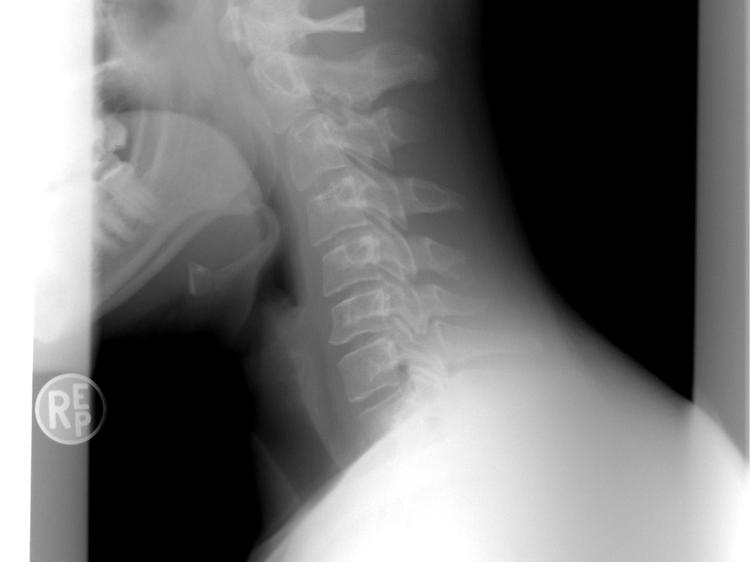

中医所说的“经络不通有结节”,是从气血运行的角度解释上肢麻木——当经络中的气血流通受阻,局部形成瘀堵结节,就会导致麻木、酸胀等感觉,这种解释在临床调理中具有一定指导意义。但从现代医学视角看,上肢麻木的原因更为复杂,常见的还有三类核心因素:一是神经压迫,比如颈椎病(颈椎间盘突出或骨质增生压迫神经根),这是上班族上肢麻木的主要诱因;肘管综合征(肘部尺神经受压)、腕管综合征(手腕正中神经受压)也很常见,多与长期用电脑、玩手机的习惯有关。二是血液循环障碍,比如上肢血管狭窄、血栓形成会导致局部组织缺血缺氧,引发麻木;久坐或长时间保持同一姿势,也会暂时影响血液循环,出现短暂麻木。三是代谢性或全身性疾病,比如糖尿病周围神经病变会损伤末梢神经,导致上肢(尤其是手指)麻木刺痛;甲状腺功能异常、维生素B12缺乏等也可能引起神经感觉异常。因此,上肢麻木不能只归因于“经络不通有结节”,需结合麻木的部位、持续时间、伴随症状(如颈痛、头晕、肢体无力)判断,最稳妥的做法是及时到正规医疗机构就诊,通过颈椎X线、神经传导速度检查等明确病因,再对症处理。